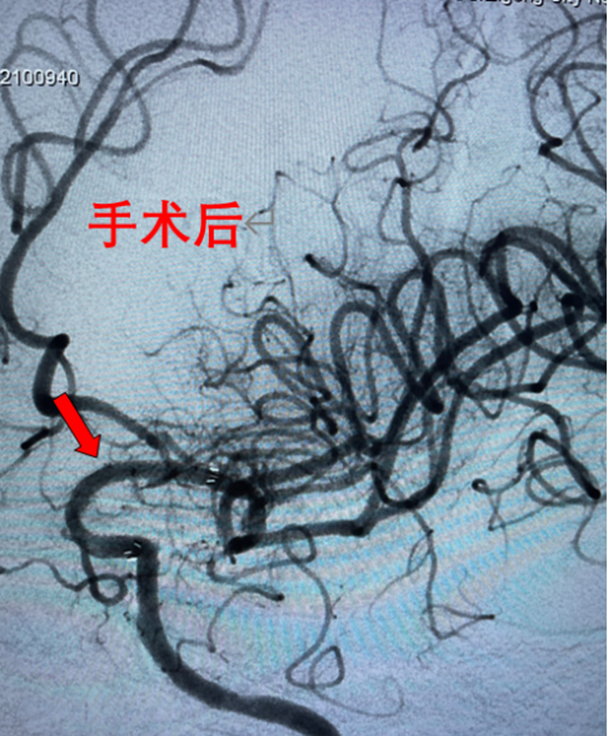

随着时间的推移,陈大爷病情不断加重,突然有一天他失去了意识,家人赶紧将他送到了自贡四院神经内科救治。经过专家的检查和诊断,陈大爷的病因找到了——左侧颈内动脉末段堵塞,导致了我们大家熟知的脑梗。

做好术前准备后,陈大爷进入介入手术室,神经内科医务人员成功为其完成了“左侧颈内动脉末段血管成形、支架植入术”。

术后,陈大爷头晕、行走不稳等症状消失,恢复到正常状态。